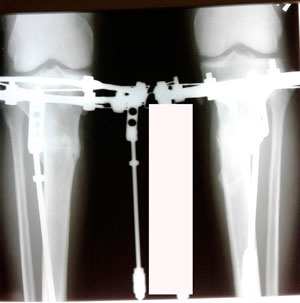

Исходник - 28 лет.

Дата операции - 27.02.2020